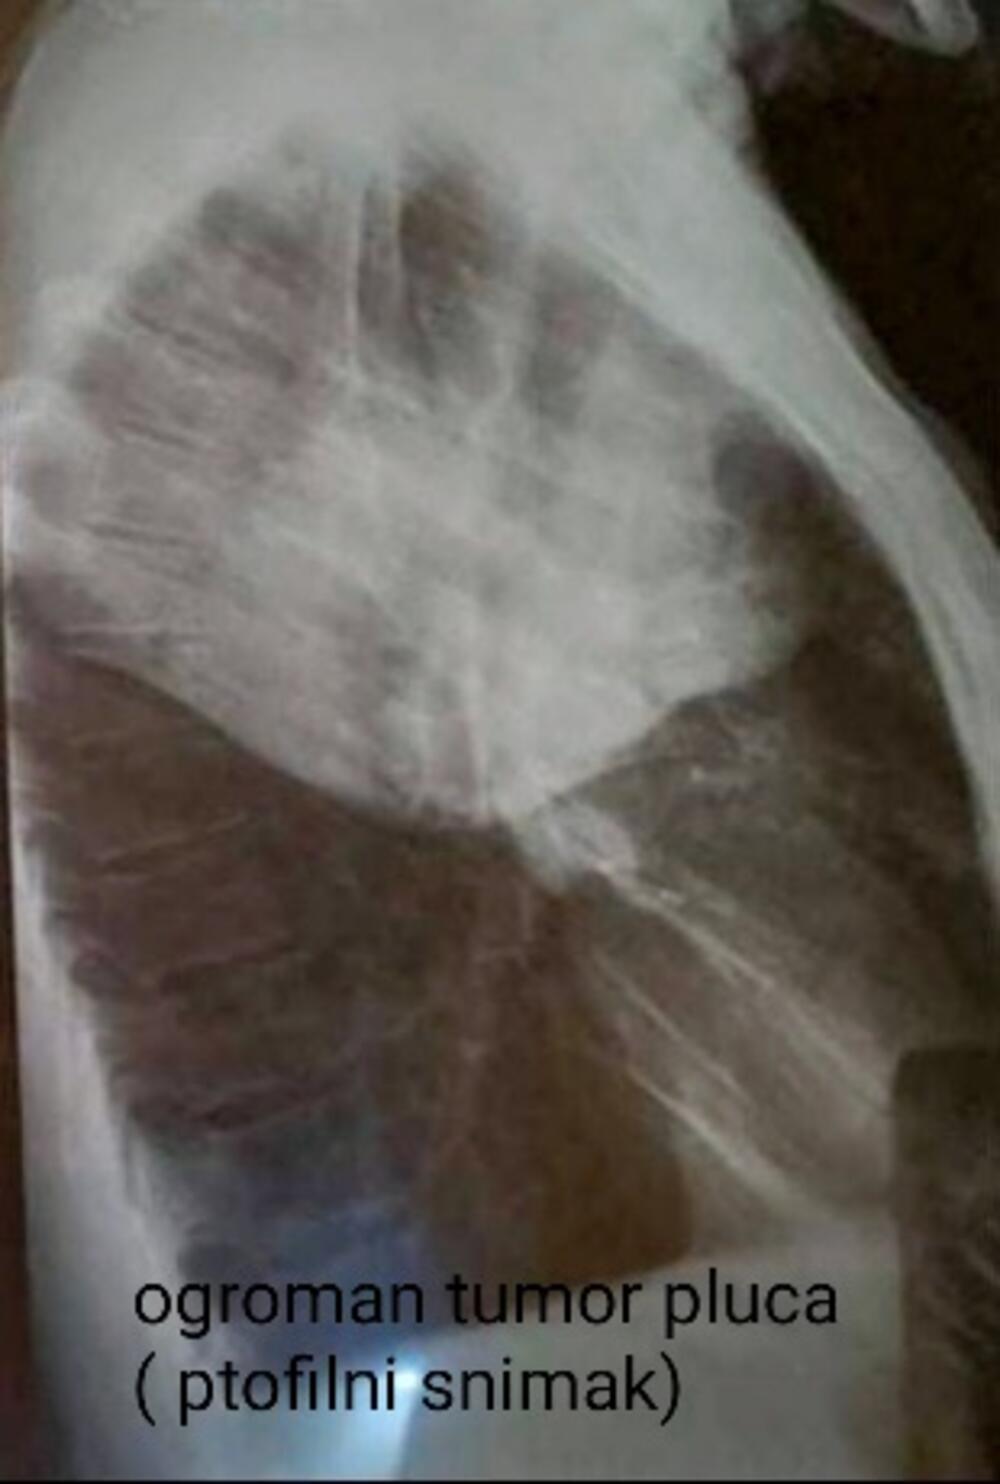

Još jedna od najčešćih bolesti u Srbiji je karcinom pluća koji je i najsmrtonosniji karcinom kod nas i u svetu.

- Prema statistici, Srbija zauzima drugo mesto u Evropi po smrtnosti, odmah posle Mađarske, a broj obolelih raste svake godine. Godišnje u Srbiji oboli 6.500 osoba, a nažalost, preko 4.600 izgubi bitku sa tom opakom bolešću. Po podacima Instituta za javno zdravlje Milan Jovanović Batut u Srbiji se svakodnevno dijagnostikuje 20 novih pacijenata, od kojih je sve više žena, a od ovog karcinoma umre 13 osoba. U svetu je, tokom 2020. godine, od karcinoma pluća obolelo oko 2,2 miliona ljudi od kojih je 1,8 miliona, nažalost, preminulo, navodi dr Slavica.

- Glavni faktor rizika za pojavu bolesti kod 90% muškaraca i 80% žena je pušenje, zatim genetski faktori i aerozagađenje. Zbog toga se pušačima posle 40. godine života, a i onima sa opterećujućom genetskom predispozicijom, savetuje da jednom godišnje urade snimak pluća. Za sve ostale, preporuka je jednom u dve godine, preventivno. Naravno, po potrebi i češće. Jedan od razloga za visoku smrtnost je kasno otkrivanje bolesti zbog nespecifičnih simptoma i nemogućnosti da se tumor otkrije u ranoj fazi zbog toga što nema dovoljno lekara niti dovoljno rendgen aparata za snimanje. Dijagnostiku je dodatno usporila pandemija korona virusa, pa je sada primetan veći broj pacijenata koji sa malignim oboljenjima dolaze u poodmakloj fazi, ističe naša sagovornica.

Ukoliko se otkrije u ranom stadijumu, uz primenu adekvatne terapije, sa karcinomom pluća može da se živi. Međutim, upravo je dijagnostika kamen spoticanja za pacijente koji imaju rak pluća.

- Pravovremenom operacijom nekih oblika tumora pluća i redovnim praćenjem može se postići potpuno izlečenje. Ako se otkrije kasno, smrtnost je vrlo visoka. Ova maligna bolest pluća može biti asimptomatska dugo vremena, čak i nekoliko godina, tako da je veliki problem što se ne otkriva na vreme, kao što je to slučaj kod drugih vrsta tumora koji daju rane simptome i za koje postoje jasni programi skrininga (karcinom dojke, grlića materice ili debelog creva), navodi doktorka Plavšić.